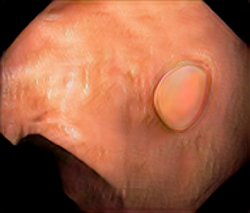

We have used a polyp dataset published with HyperKvasir dataset [51], which consists of polyp findings extracted from endoscopy examinations. HyperKvasir contains polyp images with corresponding segmentation masks annotated by medical experts. We use only this polyp dataset as a case study because of the time and resource-consuming training process of the SinGAN-Seg pipeline. However, the SinGAN-Seg model and pipeline can be used for any segmentation dataset.

A few sample images and the corresponding masks of the polyp dataset in HyperKvasir are shown in Fig 2. The polyp images are RGB images. The masks of the polyp images are single-channel images with white () for true pixels, which represent polyp regions, and black () for false pixels, which represent clean colon or background regions. In this dataset, there are different sizes of polyps. The distribution of polyp sizes as a percentage of the full image size is presented in the histogram plot in Fig 3, and we can observe that there are more relatively small polyps compared to larger polyps. Additionally, a subset of this dataset was used to prove that the performance of segmentation models trained with small datasets can be improved using our SinGAN-Seg pipeline, and the whole dataset was used to show the effect of using SinGAN-Seg generated synthetic images instead of a large dataset which has enough data to train segmentation models. In this regard, this dataset was used for two purposes: